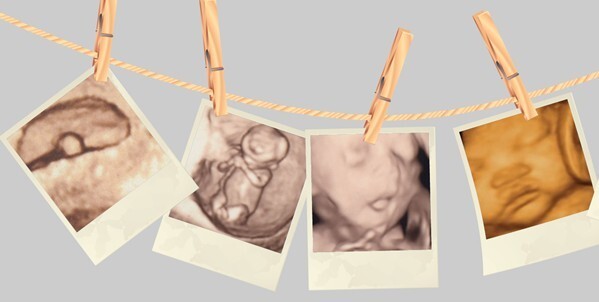

四维彩色超声诊断仪能自动为胎儿进行宫内拍“写真”和动态录像,为众多的准妈妈增添了安心和情趣。

她们不再是仅仅感觉宝宝的呼吸和运动,而且可以亲眼目睹他们的一举一动和乖巧的秀容。更为重要的是,四维彩超能够多方位、多角度地观察宫内胎儿的生长发育情况,为早期诊断胎儿先天性体表畸形和先天性心脏疾病提供依据。

过去的B超设备只能检查胎儿的生理指标,而四维彩超还能对胎儿的体表进行检查,如唇裂,脊柱裂,大脑、肾、心脏、骨骼发育不良等,以便尽早的进行治疗。生个聪明健康的小宝宝,并且将宝宝的样子和动作制作成照片或VCD,让宝宝拥有完整的0岁相册,这已经不再是幻想。